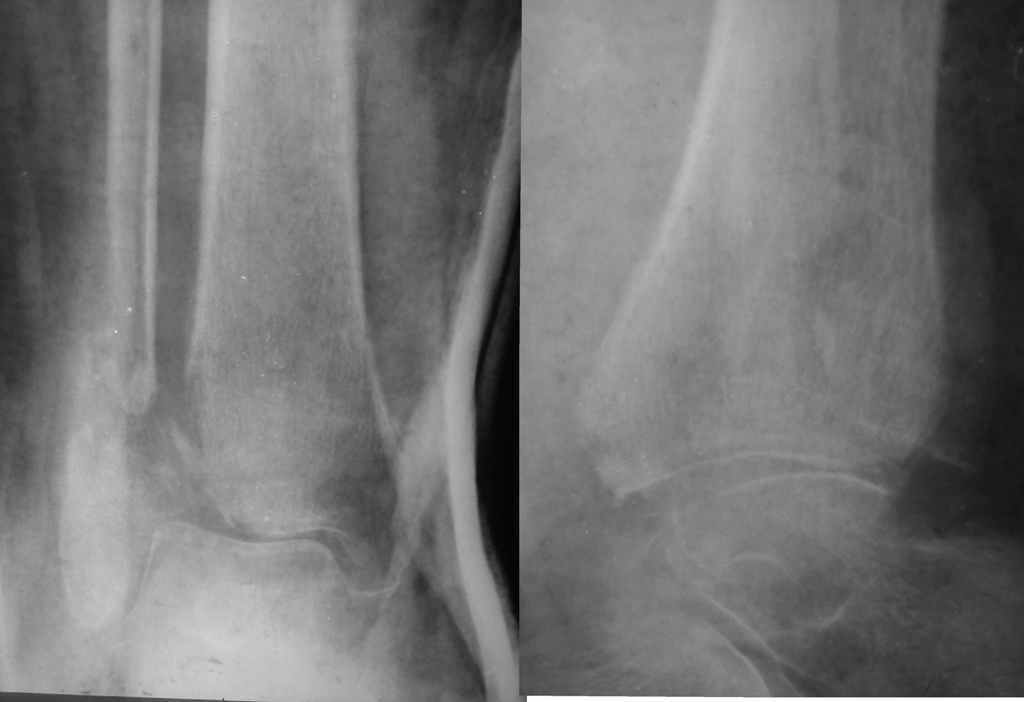

[Ortho] подвывих стопы

1955г.р. Травма 8.07.2012г. перелом открытый. На данный момент: Рана заживлена но стояние

отломков неудовлетворительное, подвывих сохраняется. Больная устала от лечения. Требует

скорейшей нагрузки на ногу. Колеги рекомендуют оставить так. Посоветуйте: нужна ли

операция? В каком объеме? Какие прогнозы при разных видах лечения?